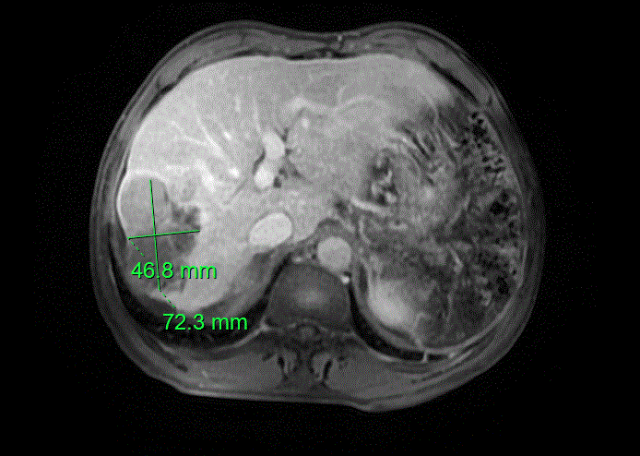

介入治疗后肿瘤大小

面对患者极其复杂的病情,科室第一时间启动多学科会诊机制,迅速集结介入科、肿瘤科、ICU等多领域专家,展开全面深入的会诊讨论。专家团队经过反复细致的研判,一致认为直接实施根治性切除术风险过高,决定先为患者开展转化治疗——即介入治疗联合靶向免疫治疗,力争通过这一方案缩小肿瘤,提升手术可切除性。在多学科团队的精准把控与协同配合下,转化治疗取得显著成效:患者的肿瘤明显缩小,身体状况逐步改善,经术前肝脏三维重建精准测量,其残余肝脏体积占标准肝体积的比例约为60%,已达到手术条件,右半肝切除术的方案就此正式敲定。